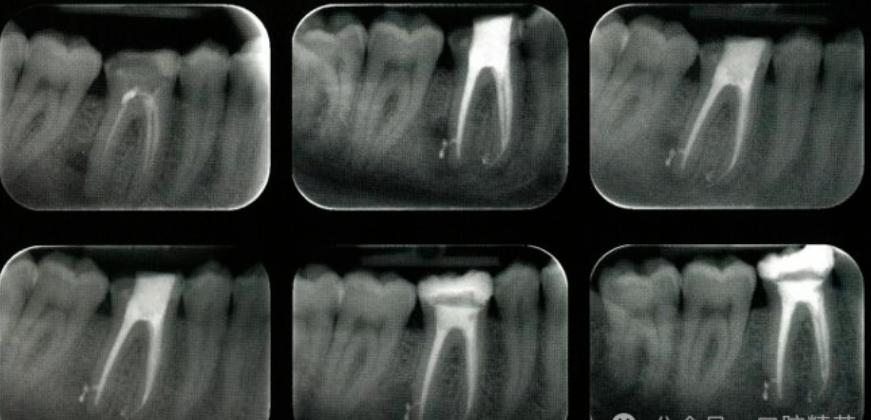

干髓术是用药物使牙髓失活,切除冠髓,将多聚甲醛干髓剂覆盖于根髓断面,通过干髓剂的作用,使根髓干燥、硬化、固定,成为无菌干化组织的治疗方法。

干髓充填。封多聚甲醛失活剂7~10天后,去除所封失活剂,去尽龋蚀组织,制备洞形,揭去髓室顶,切除已失活的冠髓,清理髓室,无水酒精干燥髓室,于根管口的牙髓断面上覆以干髓剂,磷酸锌粘固粉垫底,永久充填。

前几天接一个失败病例,在某医院做的干髓术,半年来一直有不轻不重的咬合疼。去除充填物发现开髓不全,,远中舌侧根没露出来,这个病例现在只能做根管治疗了。干髓剂一定要放在根管口。

干髓术后残髓炎的原因

(1)失活不全既封干髓剂,根管内有探痛。

(2)冠髓未去净,髓室顶未去干净髓室内有残髓。

(3)根髓未处理好,把根管口内约1MM根髓去除。

(4)根髓不干燥或出血减低了干髓剂的效果。

(5)干髓剂过稀,置干髓剂后垫底,粘固粉推压干髓剂移位。

(6)干髓剂过少,未达到保留根髓的四分之一。

(7)配制的干髓剂放置时间过长,疗效降低。

(8)失活后进行FC浴至少1分钟。

(9)干髓剂应完全覆盖根管口,如上下六一般4个根管口,不要遗漏。